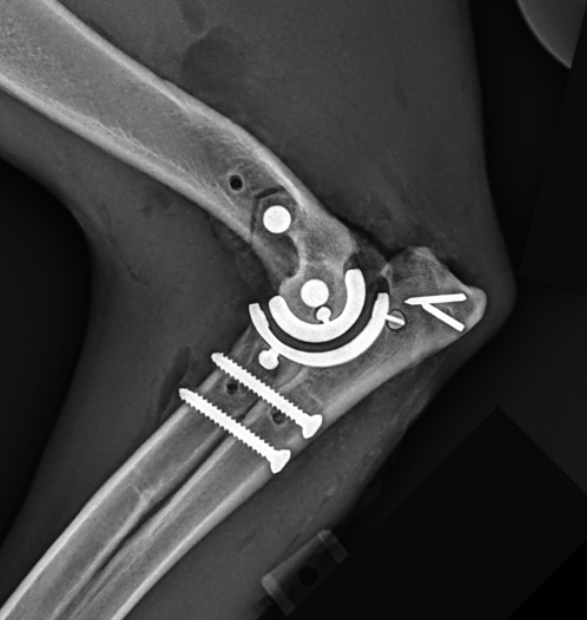

With over 20 years of experience in elbow replacement surgery, Andy has witnessed the evolution in this technology. The TATE Elbow, which was used in the 2010s at Andy’s previous clinic, marked a significant advancement in the field from the IOWA State system before that. Though it was an improvement, issues such as implant loosening posed challenges for some dogs. Now, the TATE system has undergone a complete redesign, resulting in a vastly improved third-generation implant.

"The advancements in the TATE Elbow system represent a significant leap forward in veterinary orthopaedic surgery," explains Andy. "End-stage elbow osteoarthritis is a horrible condition which can leave dogs in chronic pain and with no good treatment options. Being certified to perform third-generation TATE elbow replacements allows us to offer our patients the most advanced treatment options available, giving them the best chance for a pain-free, functional life."